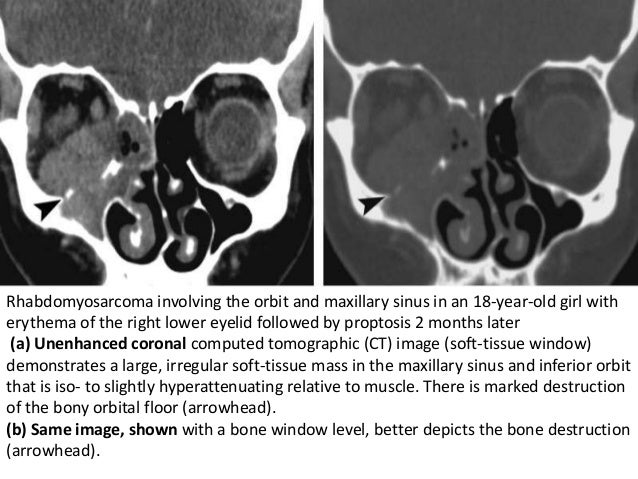

Pediatric Orbit Tumors And Tumorlike

orbit rhabdomyosarcoma tumors pediatric